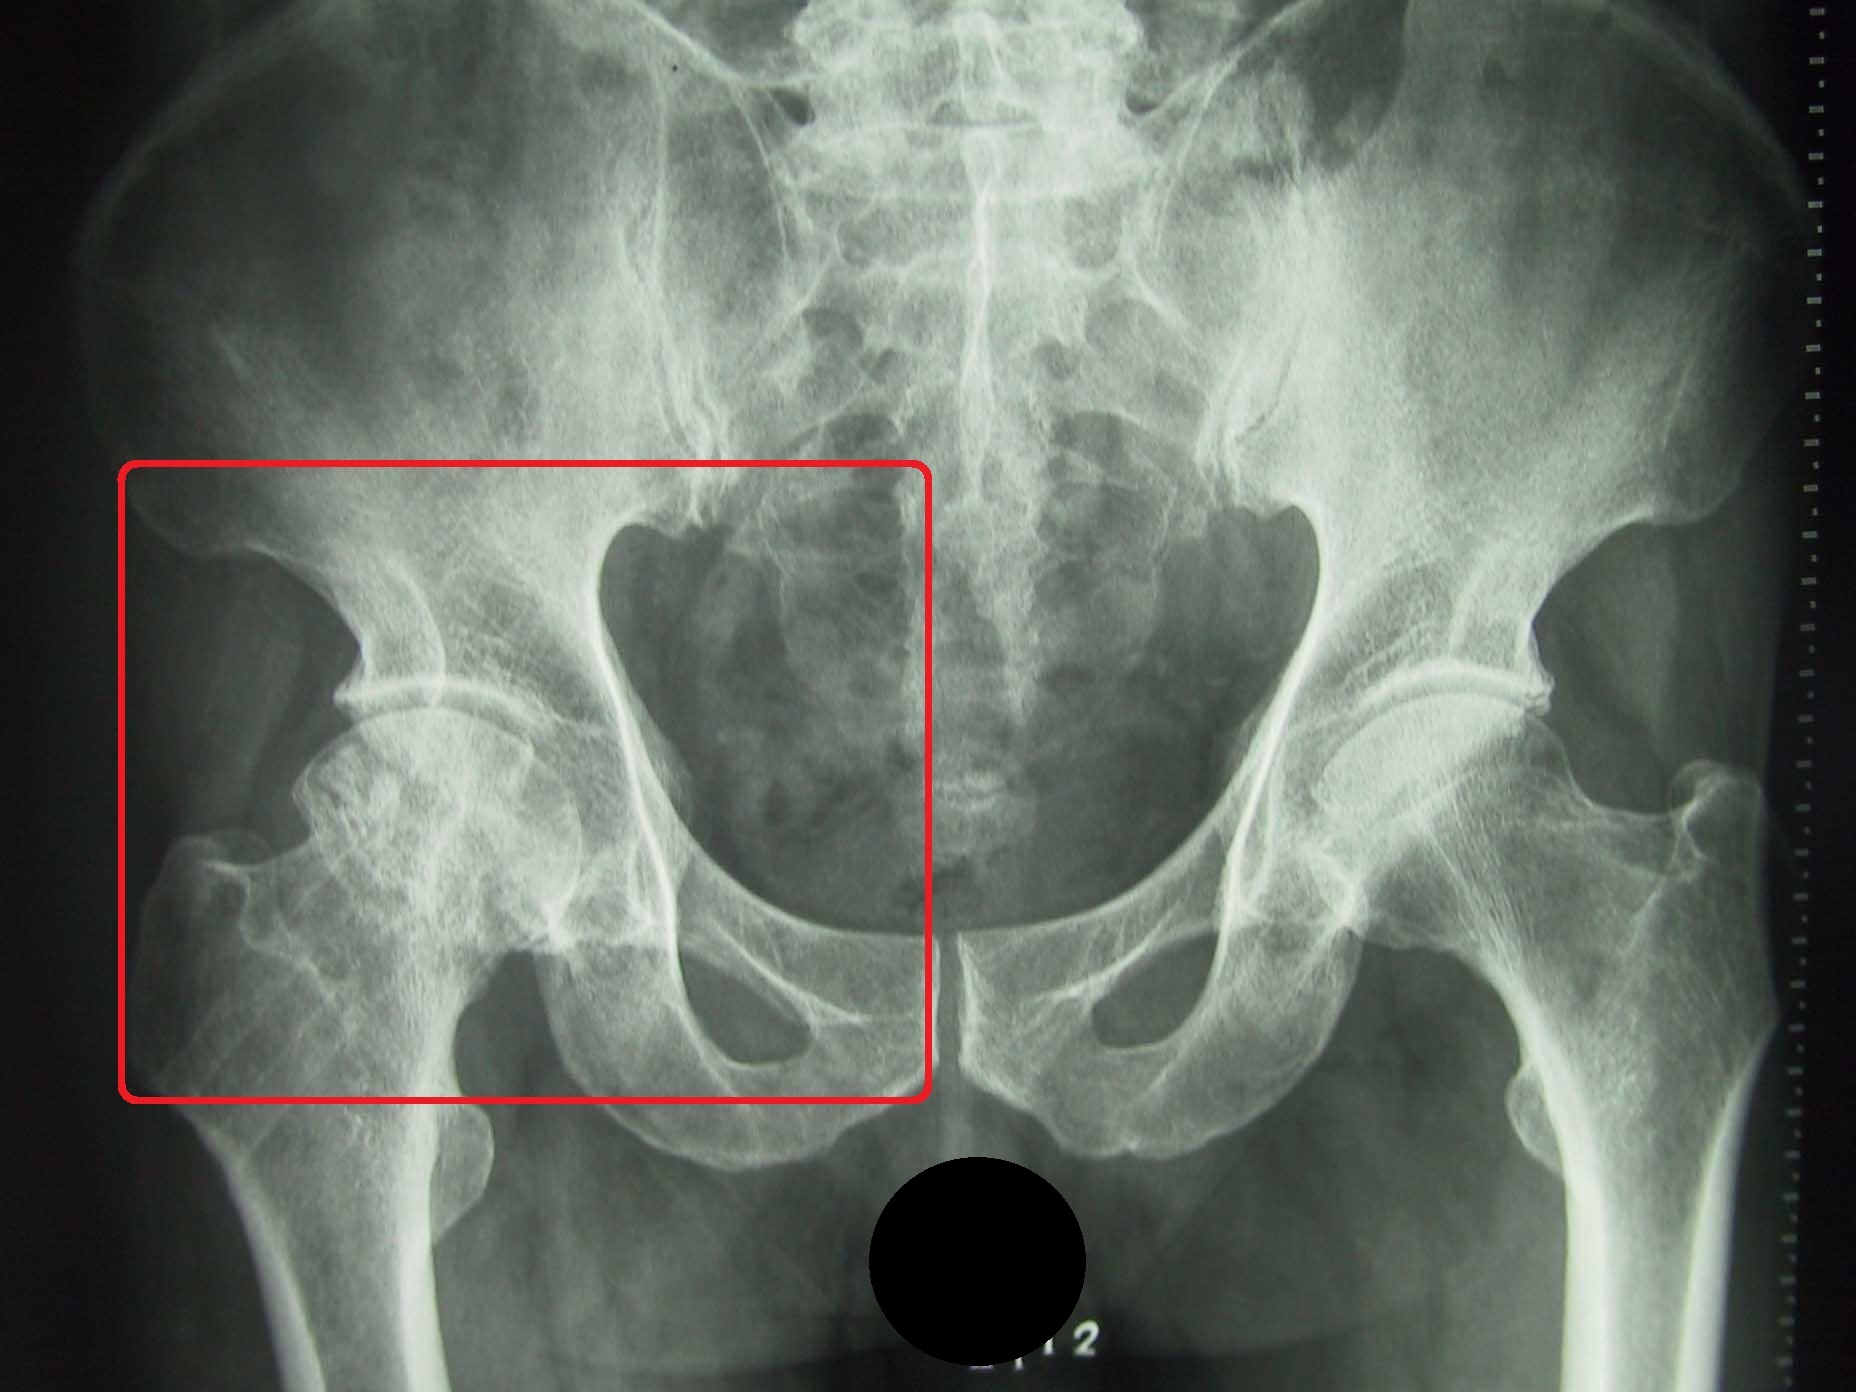

如果头还是圆的,但是股骨头里面可以看到坏死灶的话(如下图),那么这种病人可以尝试保髋手术。

目前来说保髋手术众多,但确切能减轻缓解疼痛症状的无非于股骨头钻孔减压手术了,这个手术通过小切口(相比髋关节置换来说)打钉到患者的股骨头坏死的病灶处,将股骨头局部增加的压力通过钉道释放出来,术后患者疼痛常常可以好转。

但请记住一点,钻孔减压的手术,仅仅适用于股骨头形态良好,用于延缓关节置换年限的手术,后期股骨头坏死也可能进一步加重,导致股骨头变扁塌陷需要置换的,但能延缓一年是一年咯!